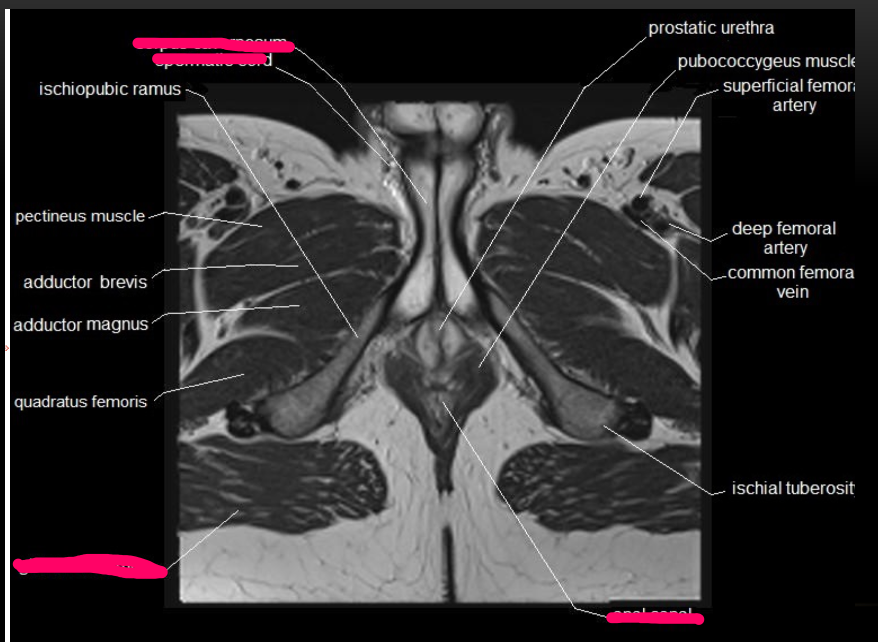

Imaging modality & complete the labels

Coronal MRI

Label & imaging modality

Coronal MRI of male pelvis